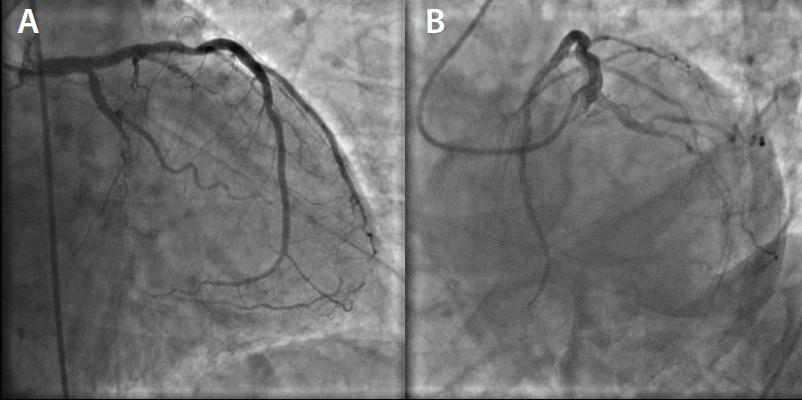

Left groin access was achieved under ultrasound guidance, and a 6-F vascular sheath was placed. Selective coronary angiography was performed in multiple views, revealing total in-stent restenosis in the mid–left circumflex artery (Figure 1). After imaging review, we decided to intervene on the lesion. Bivalirudin was started and 180 mg of ticagrelor was administered to the patient. A 3.5-F XB guide catheter was used to engage the LMCA. We were able to cross the chronic total occlusion initially using a Runthrough® guidewire (Terumo Interventional Systems). The wire was exchanged for an HT Pilot® 200 wire (Abbott Vascular) and a 0.014-inch support catheter (Figure 2). Sequential balloon angioplasty was performed from proximal to distal parts using a 1.5- X 6-mm Sprinter® OTW balloon (Medtronic), and then a 2- X 12-mm Mini Trek™ balloon (Abbott Vascular) was utilized (Figure 3). Laser coronary atherectomy was then successfully performed (Figure 4A). Postatherectomy coronary angiography revealed improved coronary blood flow (Figure 4B). Sequential balloon angioplasty was performed using a 2.5- X 20-mm Mini Trek™ balloon.

We then decided to place coronary stents. However, we had difficulty advancing the available stent even though the wire was changed to a stiffer wire and multiple techniques were attempted to no avail. We then tried a 2.5- X 24-mm EluNIR™ stent, and were able to successfully deploy the stent at the target lesion easily without any difficulty (Figure 5). We went on to deploy two more 3- X 24-mm EluNIR™ stents proximally, and finally, angioplasty with a 3.25- X 12-mm noncompliant Trek™ balloon was performed (Figures 6 and Figure 7A). Postprocedural coronary angiography demonstrated restoration of blood flow across the left circumflex artery with an excellent result (Figure 7B). At the end of the procedure, the patient left the cardiac catheterization lab stable and with no complications. The patient is discharged the next day.